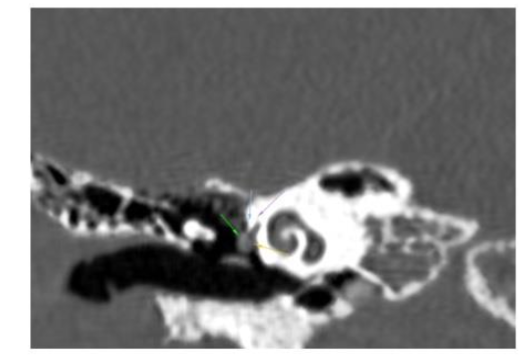

Otoendoscopy and diagnostic nasal endoscopy were normal. High resolution computed tomography (HRCT) of temporal bone showed agenesis of right stapes and dysplastic left stapes with aberrant course of facial nerve (Fig. 3, 4 & 5).

Fig.3. HRCT temporal bone – Coronal section left side showing facial nerve escaping the facial canal

Fig.4. HRCT temporal bone – coronal section left side showing only ossicular status

Fig.5. HRCT temporal bone – left side axial section showing facial nerve escaping through facial canal and coursing the promontory, through the deformed stapes